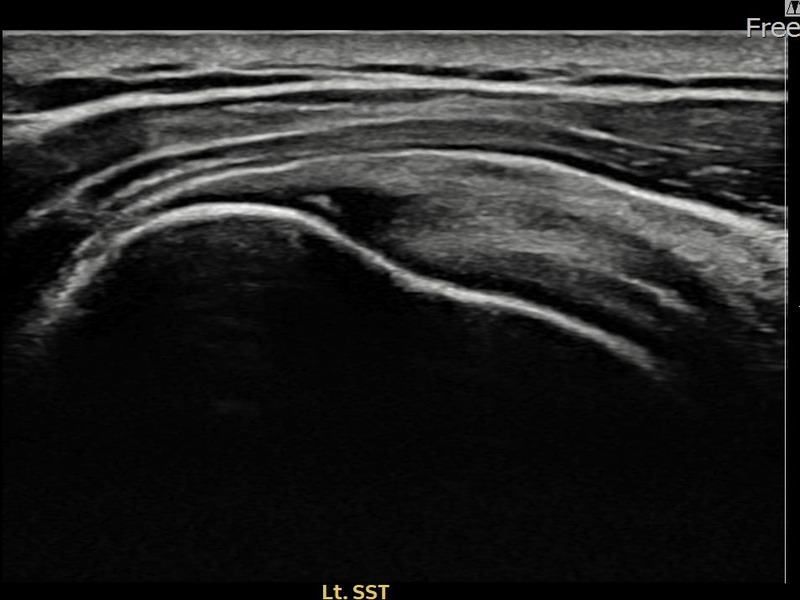

김ㅇㅇ님 · 좌측 극상근건 광범위 부분파열

좌측 어깨 광범위 파열로 수술을 권유받았으나 비수술 치료를 원해 내원하셨습니다. 초음파 검사에서 극상근건 전층에 걸친 광범위 부분파열이 확인되었으며, 어깨인대 축소봉합술 후 구조적 안정화와 기능 회복이 이루어졌습니다.